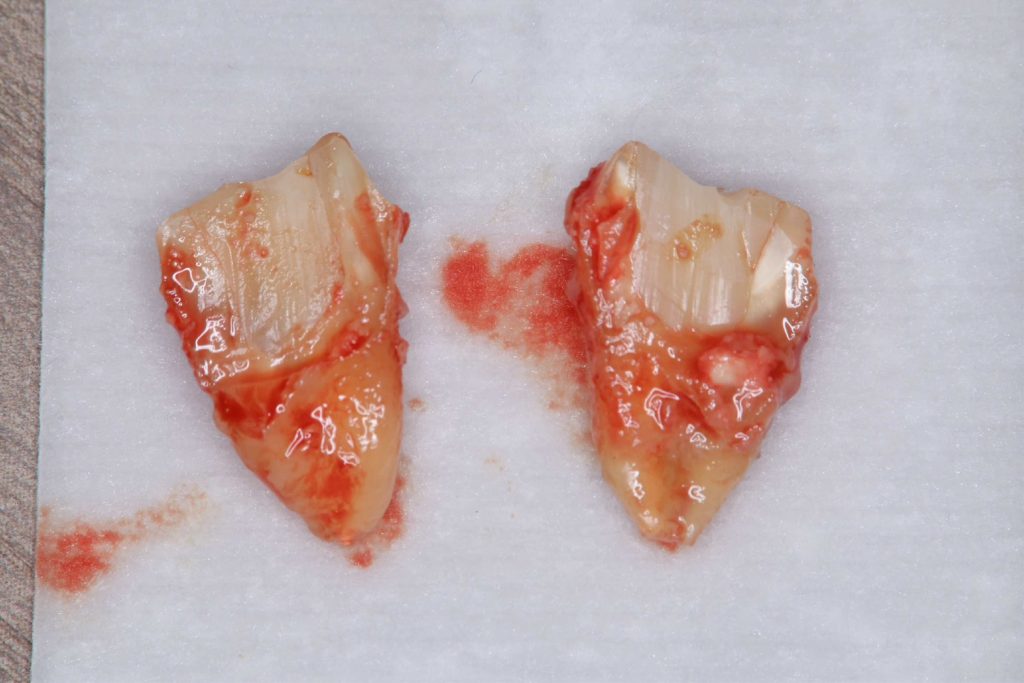

| 診断結果 | 右下7番歯根破折 |

| 治療内容 | 抜歯即時インプラント |